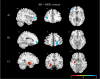

Results: Lower rsFC between the left insula and the left mid-dorsolateral prefrontal cortex and between bilateral insula and right frontopolar prefrontal cortex (FPPFC) was observed in BD compared to MDD and HC. These results were driven by the dorsal anterior and posterior insula (PI). Lower rsFC between the right amygdala and the left anterior hippocampus was observed in MDD compared to BD and HC. These results were driven by the centromedial and laterobasal amygdala. Left PI/right FPPC rsFC showed 78% accuracy differentiating BD and MDD.